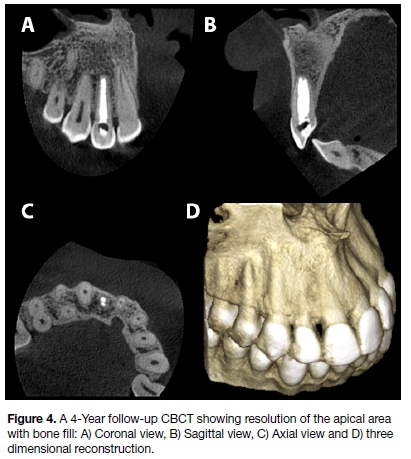

The patient was not committed to attend regular follow up visits, but was finally convinced to return for a follow-up evaluation. Four years after the initiation of the treatment, the patient was asymptomatic and the follow-up CBCT (Figure 4) showed bone fill around the right maxillary lateral incisor with complete healing of the buccal bone plate. The patient gave written consent for the use of the images and radiographs for publication.

CASE DESCRIPTION: A healthy 21-year old male presented with pulpal necrosis, a large periapical lesion, incomplete root formation and an open apex on a maxillary right lateral incisor. Triple antibiotic paste was used to achieve antimicrobial control after traditional calcium hydroxide paste medicament failed to resolve the symptoms. Obturation was achieved using MTA and the conventional apexification technique. Excellent healing of the large periapical lesion was achieved without surgical intervention and the 4-year follow-up CBCT demonstrated complete bone All of the lesion.